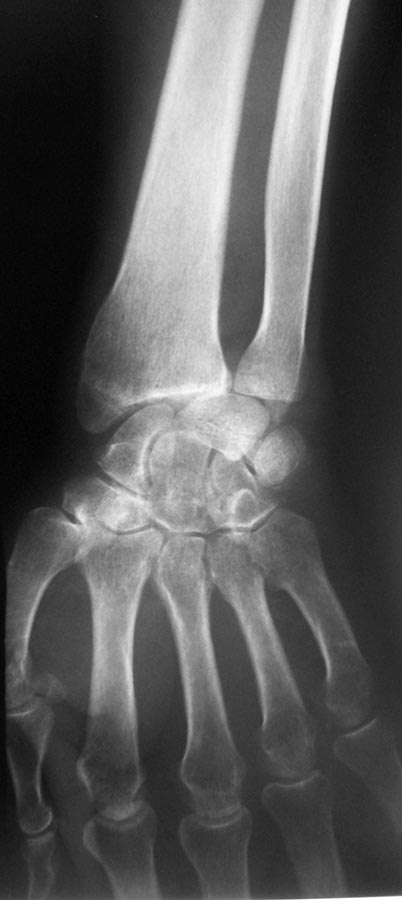

Поступил пациент В, 49 лет. С жалобами: на ограничение движение в правом лучезапястном суставе, на жжение в пальцах правой кисти в ночное время. Анамнез: получил травму 25.12.2015 г. лечили амбулаторно перелом лучевой кости, наложена гипсовая лонгета. После снятие гипса легча не стало. Амбулаторные снимки прилагаются. Выполнили КТ DS: признаки вывиха полулунной кости, срастающийся перелом лучевой кости дистального эпифиза, трехгранной кости. Нужна помощь в тактике лечения.

По этому единственному снимку больше на вывих ладьевидной похоже. Одного снимка маловато.

Извиняюсь, вот от 20.02.2016 снимки.

Коллеги, пожалуйста, покажите, где на снимке вывих полулунной кости. Я фиксирую 1 спицей, на 6 нелель, после открытого вправления. По букварю, необходима дистракция перед вправлением.